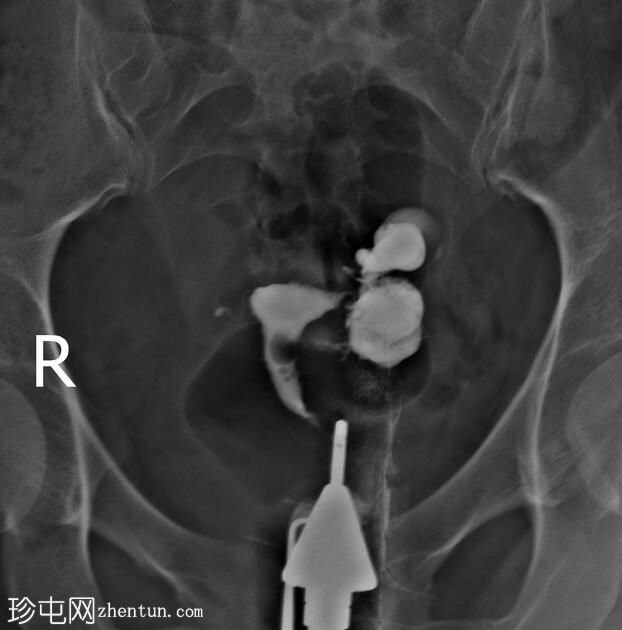

子宫位于盆腔正中线,形态及轮廓正常。

宫颈管长度及黏膜表面正常,扩张正常。

左侧输卵管充盈,管腔扩张,造影剂残留,无因输卵管积水导致的溢液。

右侧输卵管峡部造影剂显影中断,造影剂远端呈球状扩张。